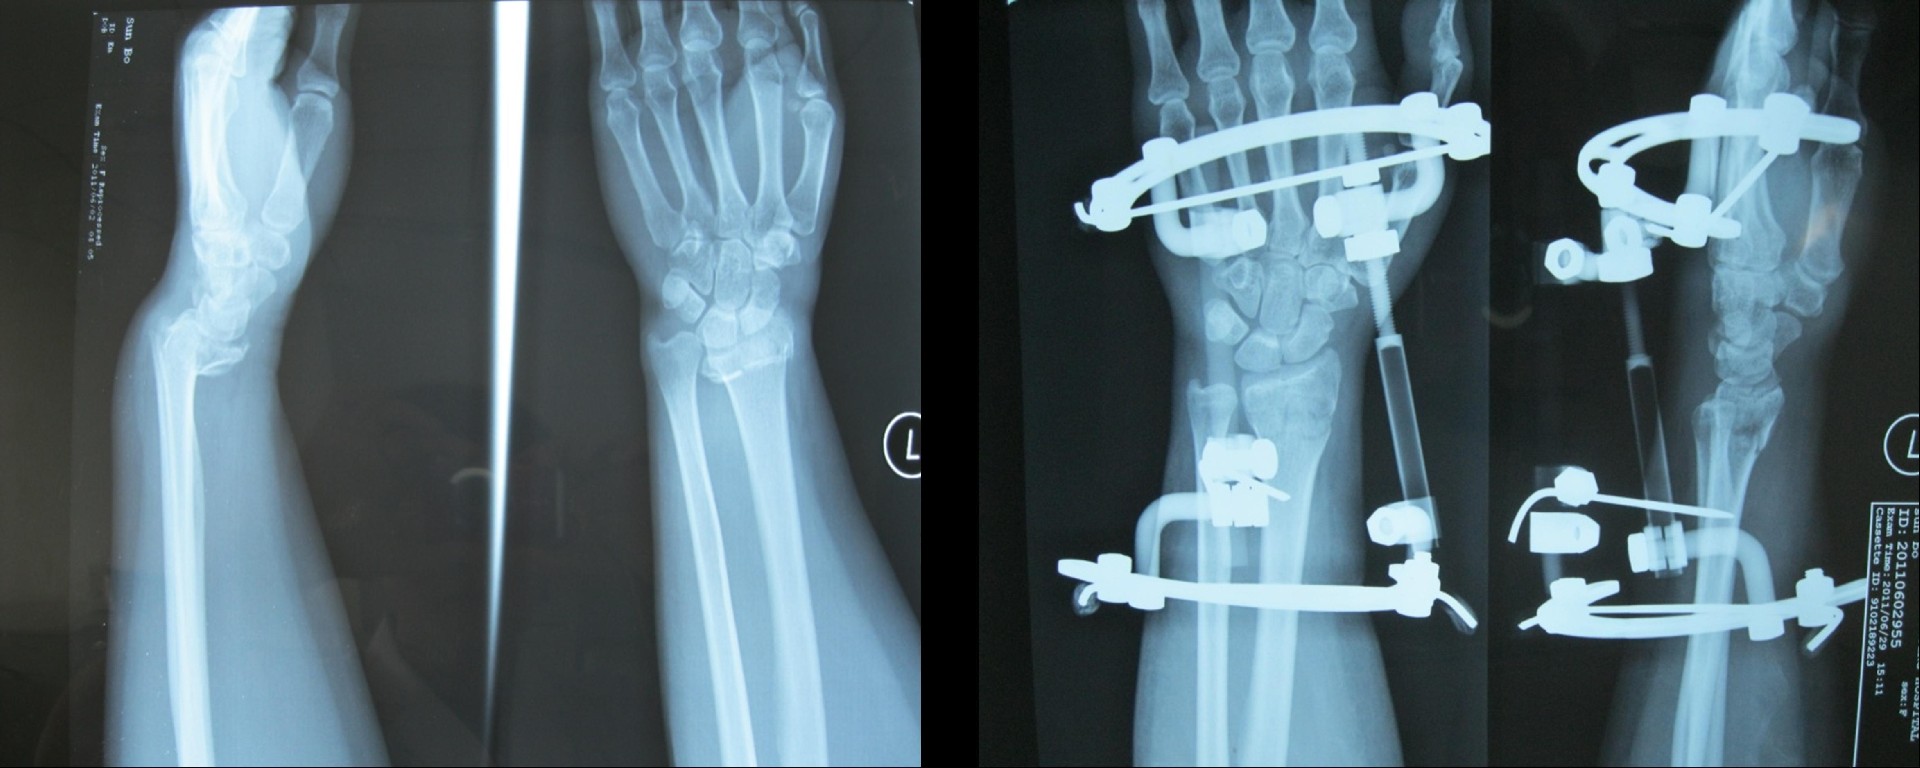

橈骨遠(yuǎn)端骨折術(shù)前

橈骨遠(yuǎn)端骨折術(shù)后

橈骨遠(yuǎn)端骨折術(shù)前 橈骨遠(yuǎn)端骨折術(shù)后

五研獨(dú)家產(chǎn)品組合式腕關(guān)節(jié)骨外定架,具有專利保護(hù)

組裝簡便,穿針便捷,適合各種橈骨遠(yuǎn)端骨折及腕部矯形。斷端無X線遮擋。